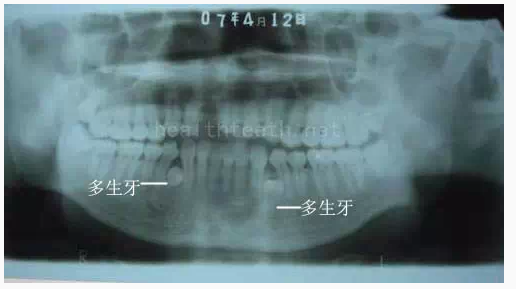

病例3,同時多生兩顆牙齒